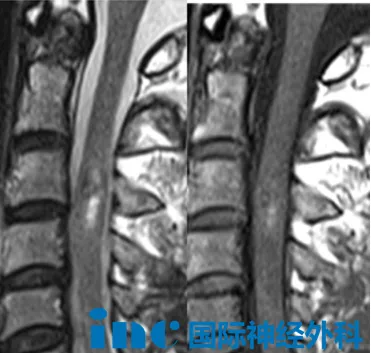

51岁的潘先生,颈髓C2—C4节段存在约6mm×18mm的异常信号灶,进一步影像评估提示颈髓海绵状血管瘤伴出血可能。病程中,左上肢麻木、酸痛感持续进展,症状范围逐步扩大,脊髓功能受累呈动态加重趋势。综合评估病灶部位、出血风险及神经功能损伤的进展情况,核心临床顾虑在于:一旦发生新一轮脊髓内出血,极可能造成不可逆的感觉或运动功能障碍,致残风险不容轻视。为此,潘先生选择尽早接受手术干预,主动规避神经功能进一步受损的风险。

术前谈话中,巴特朗菲教授基于对病灶现状与手术时机的系统研判,明确指出:当前病灶仍处于可干预阶段,手术时机选择恰当,术后功能恢复的预后预期良好。